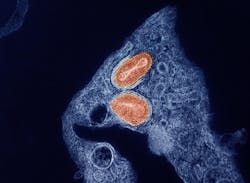

According to a Study of Tecovirimat for Mpox (STOMP) analysis, “tecovirimat did not reduce the time to lesion resolution or have an effect on pain among adults with mild to moderate clade II mpox and a low risk of developing severe disease.”